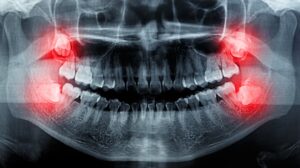

The most definitive way to determine if your wisdom teeth are impacted is through dental X-rays. A dentist can evaluate the position of the teeth and recommend treatment based on their findings. If you experience any of these symptoms or suspect that your wisdom teeth may be impacted, consulting with a dentist for a professional evaluation is essential.

No, not everyone develops wisdom teeth. Some people are born without one or more of these molars. Others may have them fully formed but they remain beneath the gums. Dental X-rays can confirm whether wisdom teeth are present and how they are positioned.